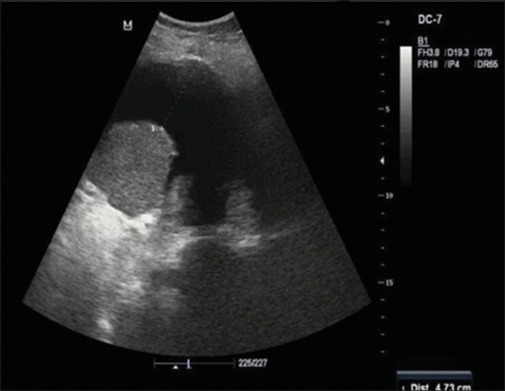

Methods: Patient with residual hemothorax (>200 mL) on ultrasonography after 48 h of indwelling ICT was randomized into either early video-assisted thoracic surgery (VATS) or conventional approach cohort. Early VATS cohort was subjected to video-assisted thoracoscopic evacuation of undrained blood along with normal saline irrigation and ICT placement. The conventional cohort underwent intrapleural thrombolytic instillation for 3 consecutive days. The outcome measures were the duration of indwelling ICT, removal rate of tube thoracostomy, length of hospital stay, duration of intensive care unit (ICU) monitoring, need for mechanical ventilation, incidence of pulmonary and pleural complications, and requirement of additional intervention to address undrained hemothorax and mortality rate.